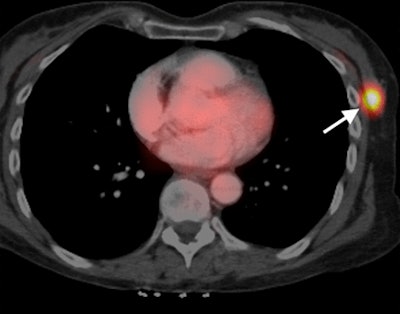

California researchers have found links between the appearance of triple-negative breast cancer on two different imaging modalities, MRI and PET/CT. They believe their findings can help guide therapy for the disease, which occurs less frequently but is typically more deadly than other types of breast cancer, according to a study published online July 22 in Radiology.

Researchers from the University of California, San Francisco (UCSF) found a strong association between dynamic contrast-enhanced (DCE) MRI signal enhancement ratio and maximum standardized uptake values (SUVmax) from PET/CT scans. The relationship could help illustrate the progression of triple-negative breast cancer and be a valuable tool to assess a patient's prognosis, they concluded.

Because DCE-MRI and FDG-PET/CT can visualize the functional properties of breast tumors, the modalities have increasingly been used to evaluate invasive breast cancer. DCE-MRI, for example, can quantify tumor progression through signal enhancement ratios, while SUVmax as measured by FDG-PET can indicate breast cancer metabolic activity.

FDG-PET/CT examinations were performed on a PET/CT system with a 16-slice CT device (Biograph 16, Siemens) or a 64-slice CT system (Discovery VCT, GE). Patients received 12.5 mCi (± 2.5 mCi) of FDG, with scans starting approximately 60 minutes (± 15 minutes) thereafter.

Patients were also given a 150-mL injection of iohexol (Omnipaque 350, GE) for the CT scans, with PET exams conducted in 3D mode with seven to 10 bed positions immediately after CT.

For SUV measurement, PET, CT, and fused PET/CT images had a region of interest placed over any FDG-avid breast focus by two radiologists who were blinded to MRI results and patients' pathologies.